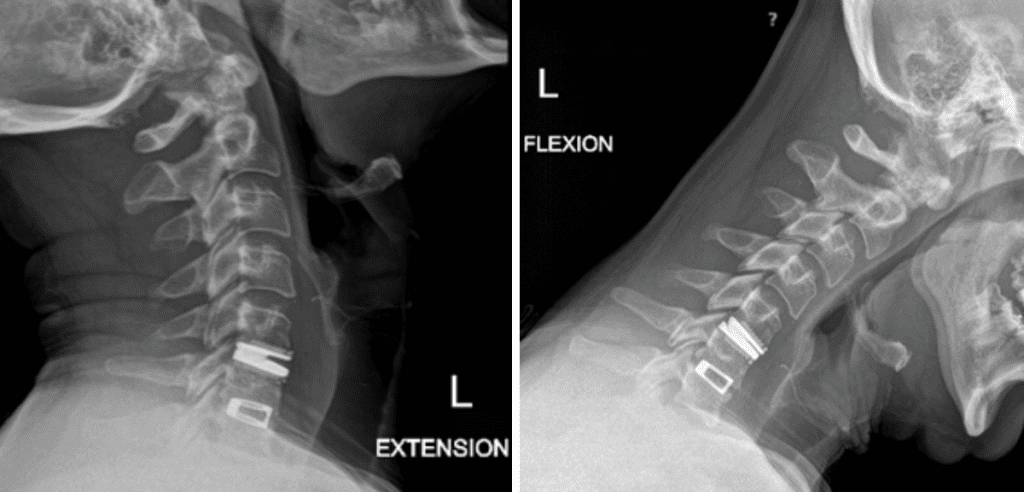

This is a 42-year-old otherwise healthy male who presented electively with progressively worsening neck pain radiating down the left arm, with paresthesia first three digits. He […]